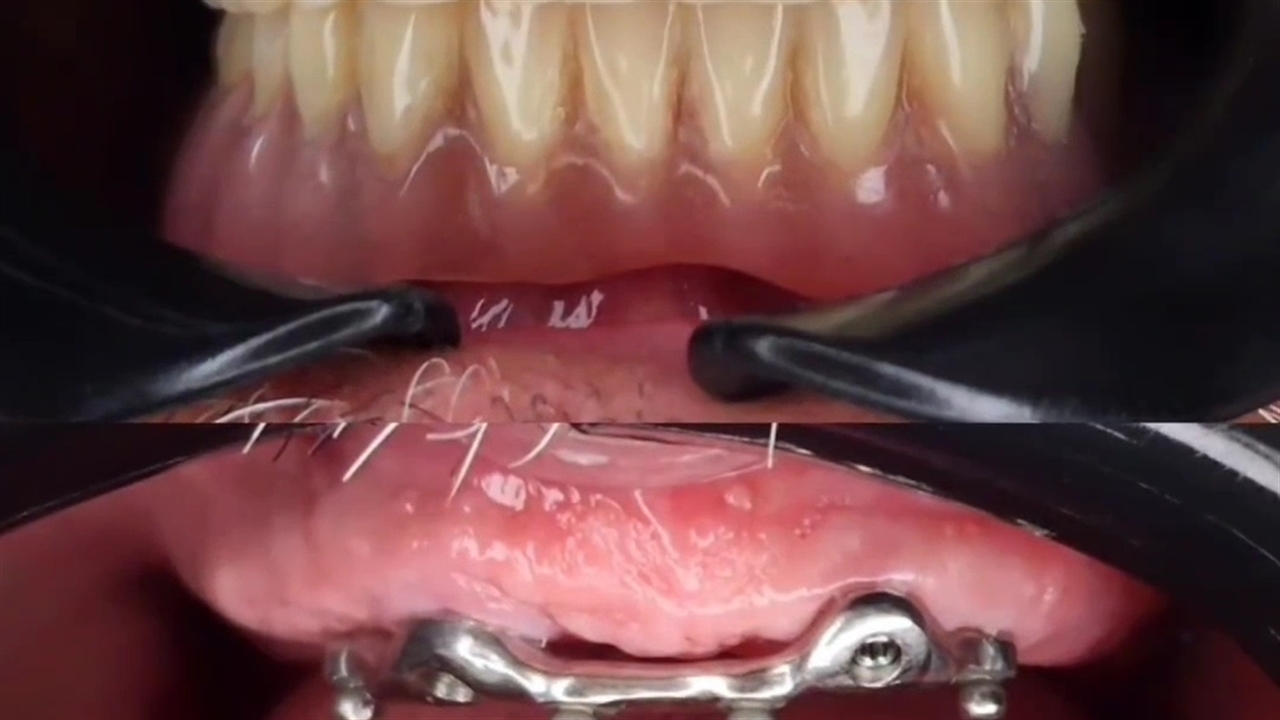

بهترین دندانپزشکی در اصفهان، دندانپزشکی دکتر کچوئی و دکتر کامران می باشد که در قالب یک مرکز و کلینیک دندانپزشکی ارائه دهنده کلیه خدمات عمومی و تخصصی دندانپزشکی زیبایی، ایمپلنت،کامپوزیت ونیر، درمان ریشه (عصب کشی)، دندانپزشکی کودکان و نوجوانان و... ، یکی از مجهز ترین مطب های دندانپزشکی در سطح استان اصفهان می باشد.